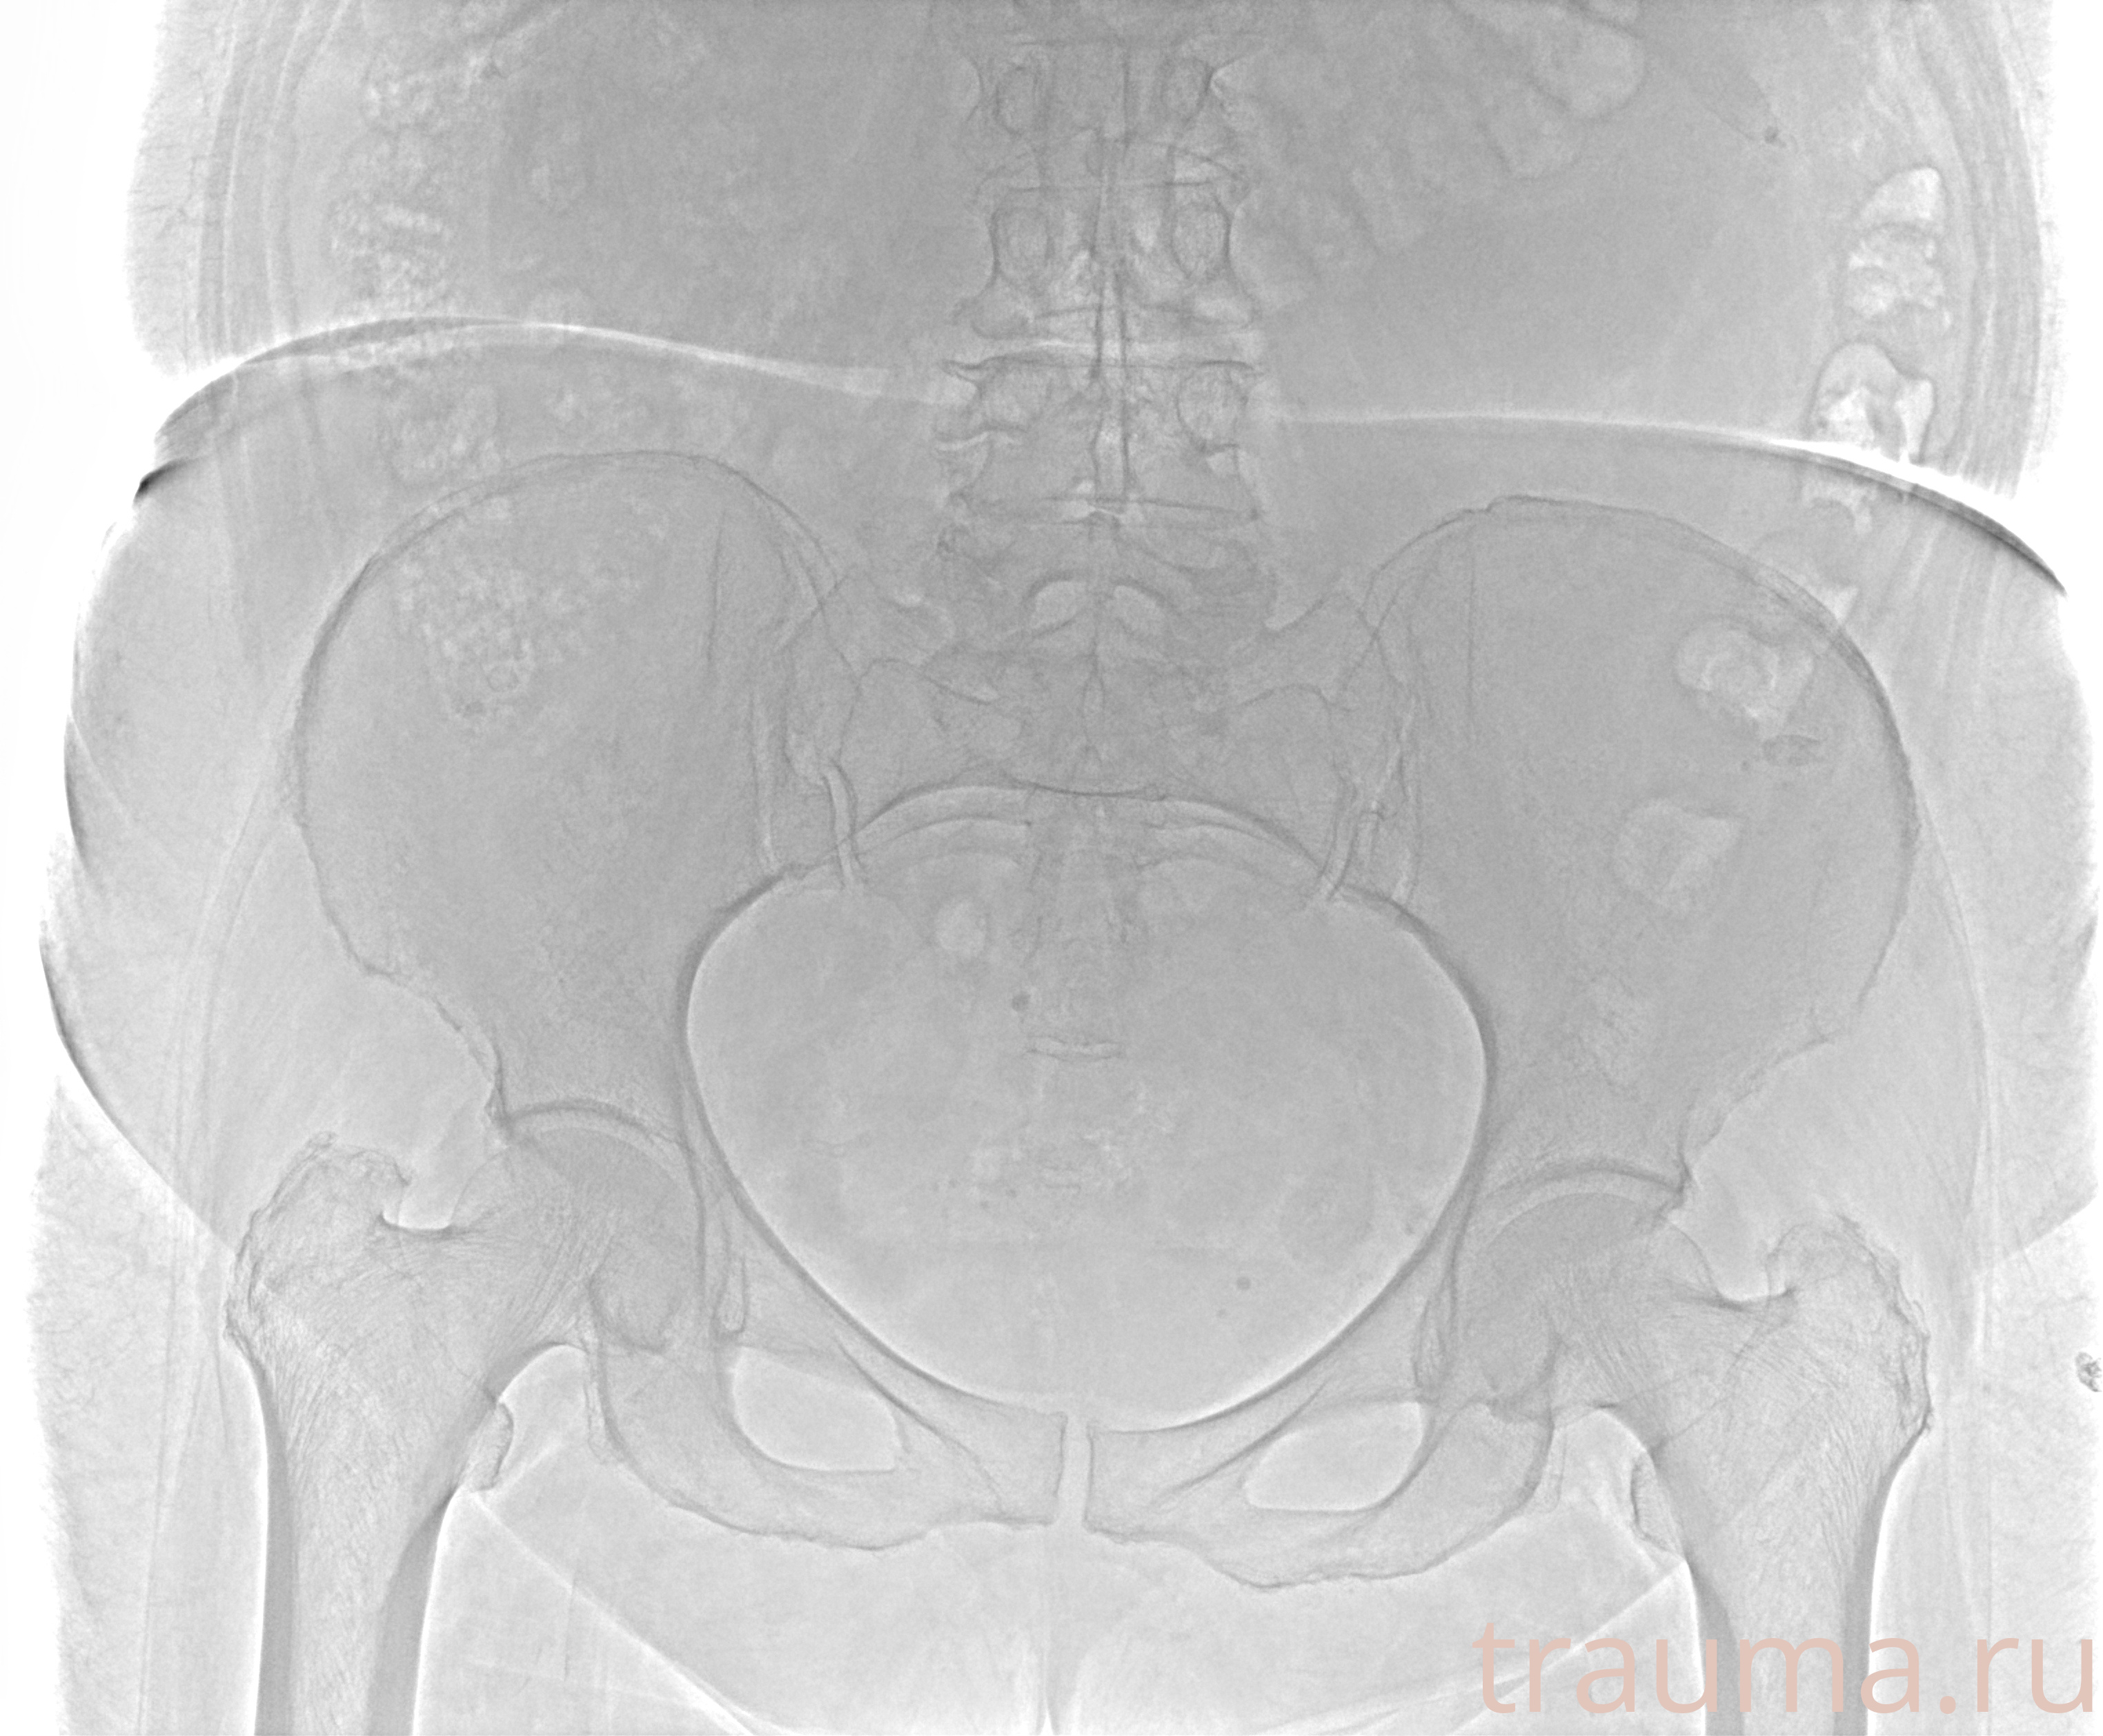

Рентгенограммы